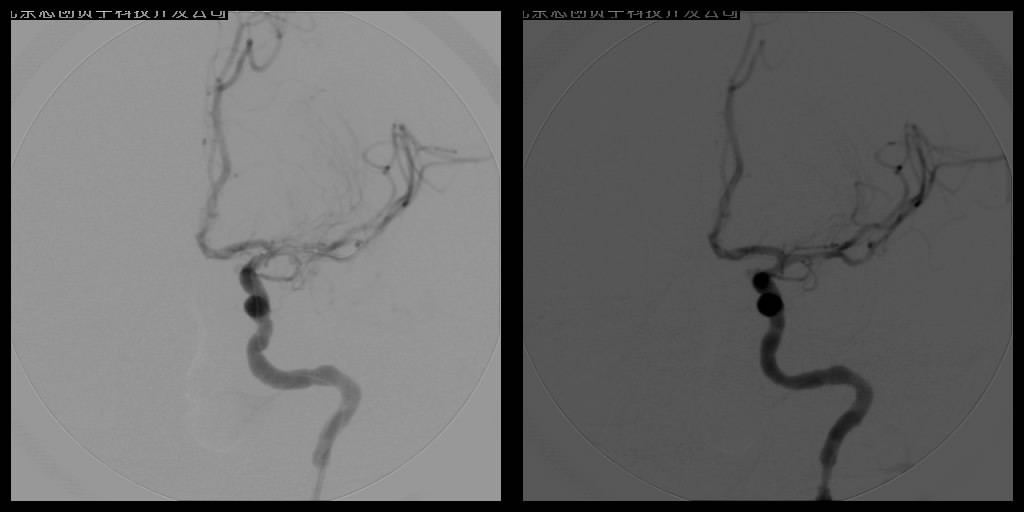

动脉支架植入术

血管球囊扩张成形术和血管内支架植入成形术已经成为治疗脑缺血、脑梗塞十分重要的手段。手术操作时在DSA监控下,将导引管经主动脉插到供应颅脑的血管——颈动脉或椎动脉内,再置放支架,达到扩开狭窄段血管、顺性行血流再建的目的,所用支架可分为球囊扩张式支架和自膨式支架。DSA系统辅助下的动脉血管成形术不但能清晰明确地了解影像病变,而且在造影过程中就可了解血管内血流、血管壁等情况,全面判断血管结构及功能变化,为确诊和治疗提供了可靠的依据,已在临床上取得了良好的疗效。